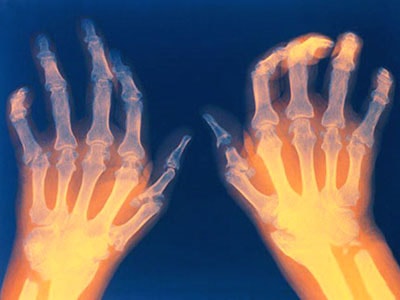

На рентгенограмме пораженные суставы эрозированны, суставные поверхности сужены. Характерно также наличие остеопороза и остеолиза со смещением пальцев. В более запущенных случаях опрделяется сращение костей — анкилоз и кальцификация.